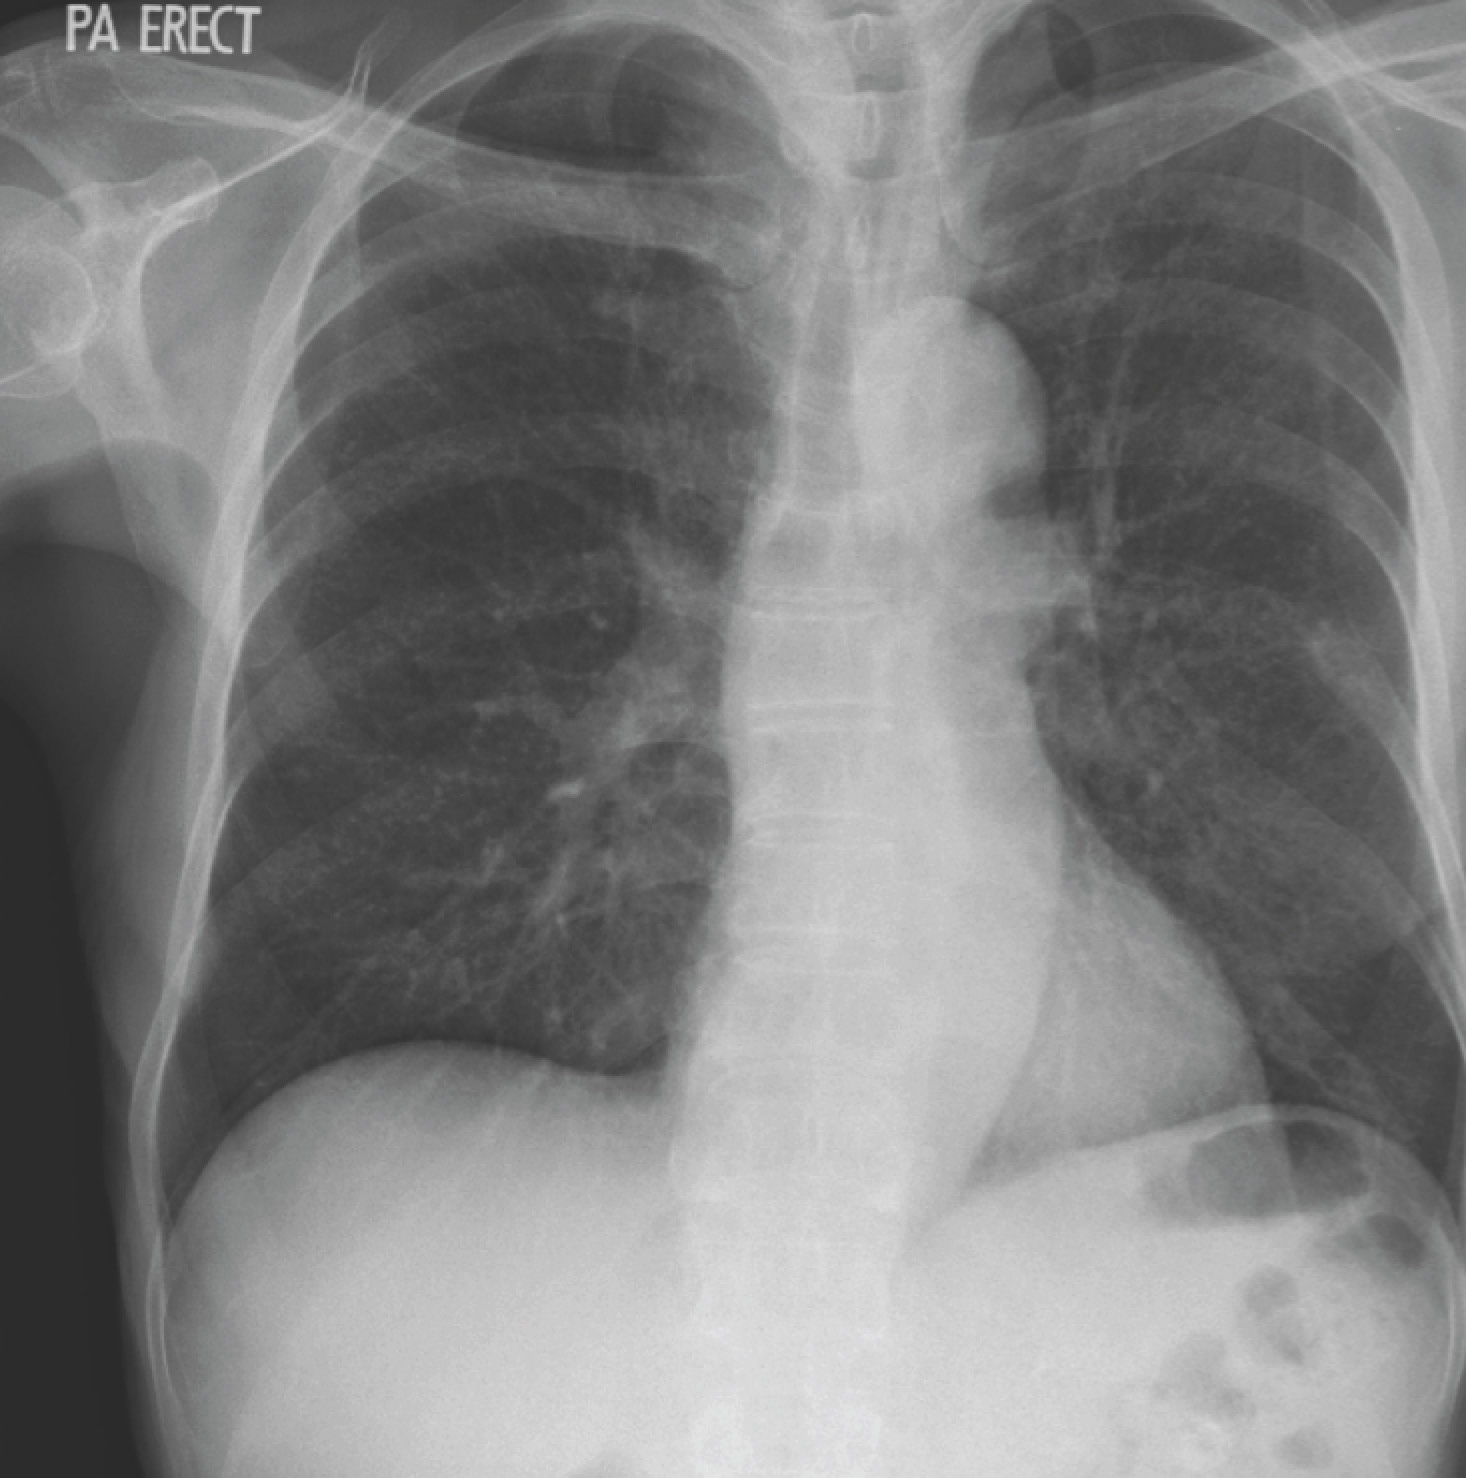

His chest X-ray and a representative cut from the CT thorax is shown below.

The CT (it’s much harder to appreciate on the chest X-ray) shows “millet-like” nodules over the lung fields. The second sputum specimen sent was positive for acid-fast bacilli on microscopy, and both sputum samples grew Mycobacterium tuberculosis. This man had miliary tuberculosis, so termed because of the appearance of the many tiny lung nodules on histology. Although the risk of mortality is higher than “ordinary” pulmonary tuberculosis, treatment is the same.